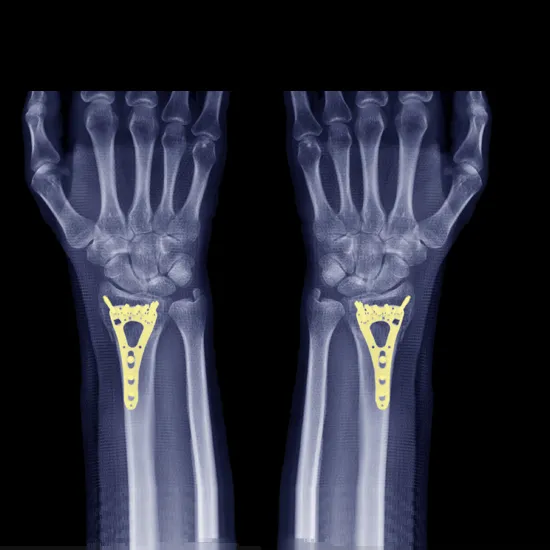

NCCT Right Hand is the non-contrast computed scan of the right hand to visualise the right hand and its surrounding tissues. The scan uses motorised X-rays with computer technology for the diagnosis of the abnormalities in the right hand.

In this scan, you need to lie prone on the table and affected hands are placed in the centre of the scanning table and the head can rest on the other arm sides, then scans are performed.